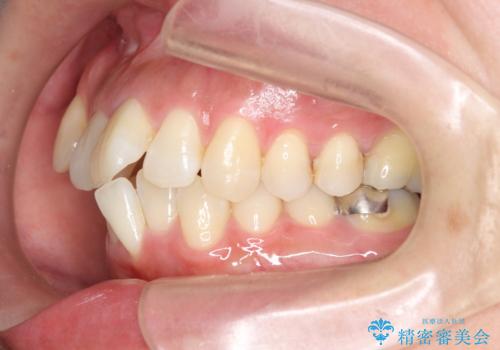

職業柄ワイヤー矯正ができない、マウスピース矯正で行う八重歯抜歯症例

- 「長年気になっている八重歯を矯正治療で治したい、ただし職業柄ワイヤー矯正は絶対にできないのでマウスピース矯正を希望。」

、と矯正治療を希望され来院されました。

通常は八重歯の抜去は行わず、小臼歯の抜去を行いワイヤー矯正を行いますが、八重歯を抜去することでマウスピースで現実的に達成できる機能的な歯並びを獲得できるよう治療計画を立案します。

治療に制約がある場合でも、現実的な治療ゴールを設定することで機能的・審美的な歯並びを手に入れることができました。